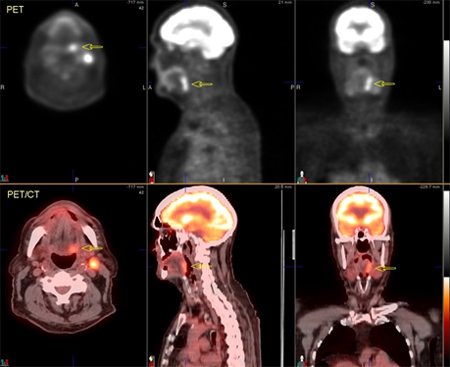

[Figure caption and citation for the preceding image starts]: 60-year-old man with squamous cell carcinoma of the right tongue base. Fluorodeoxyglucose PET/CT images demonstrate focal increased metabolic activity in the right tongue base, which extends inferior to the hypopharynx (arrows) and across the midline. On the CT images (top row), soft-tissue irregularity can be seen, but the margins of the tumour are difficult to defineFrom the collection of Dr Fabio Almeida; used with permission [Citation ends].